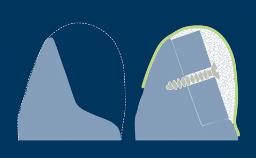

骨膜松弛切口 (PRI)

骨膜松弛切口 (PRI) 是一种常见的口腔外科手术技术,用于增加手术翻瓣的活动性。如果操作正确,骨膜松弛切口可使龈瓣冠向复位,从而实现手术部位的无张力一期关闭。